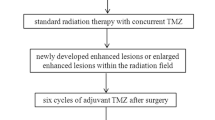

Seventy-two consecutive patients with post-GKRS metastatic brain tumor were enrolled. Two readers independently calculated the percentile histogram cutoffs for normalized cerebral blood volume (nCBV) from dynamic susceptibility contrast (DSC) imaging and initial area under the time signal-intensity curve (IAUC) from DCE imaging, respectively. Area under the receiver operating characteristic curve (AUC) and interreader agreement were assessed.

For differentiating tumor recurrence from therapy effect, adding DCE imaging to diffusion-weighted imaging (DWI) significantly improved AUC from 0.79 to 0.95 for reader 1 and from 0.80 to 0.96 for reader 2, respectively. There was no significant difference of AUC between the combination of DWI with DSC imaging and the combination of DWI with DCE imaging for both readers. With the combination of DWI and DCE imaging, the sensitivity and specificity were 86.7 and 88.1 % for reader 1 and 90.0 and 85.7 % for reader 2, respectively. The intraclass correlation coefficient (ICC) between readers was highest for calculation of the 90th percentile histogram cutoffs for IAUC (ICC, 0.87).